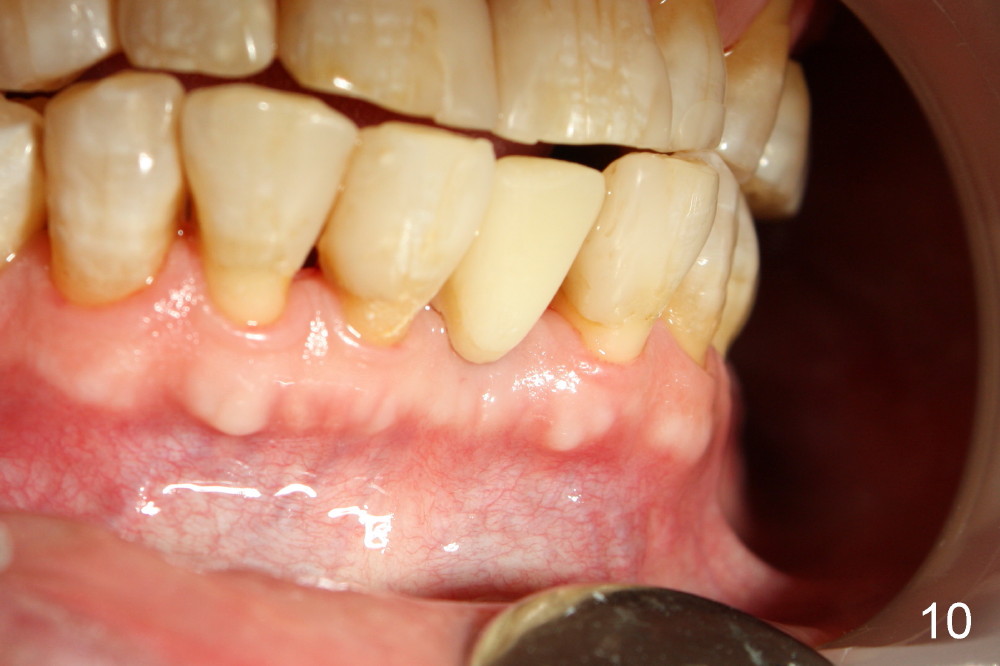

Fig.10,11 show 7 day follow up.  The permanent crown is seated 4.5 months postop (Fig.12).  Minimal bone resorption occurs at the crest 4 months postop (Fig.13), which is most likely associated with conservative approach (flapless).  The patient returns for follow up 2.5 months post cementation (Fig.14,15).  The implant remains in the bone 4 years post cementation (Fig.16 CT coronal section; lingual thread exposure, corresponding to preop defect in Fig.1).   There is mild coronal bone resorption 5 years 4 months post cementation (Fig.17).